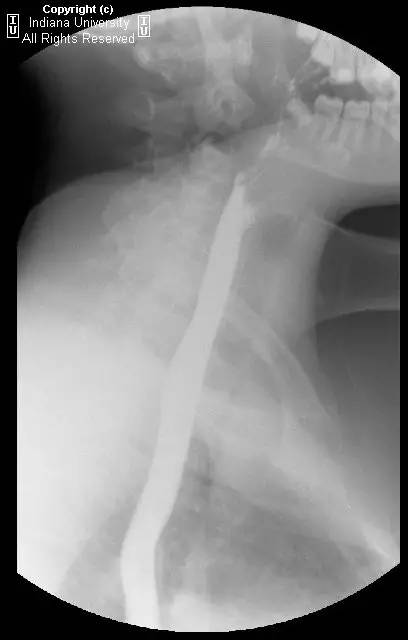

【影像学表现】可见小滑动性食管裂孔疝,食管远端胃食管连接处上方亦见一小的边界清晰的环形充盈缺损,钡剂通过顺利,但直径13mm不透射线的药片吞水后仍在充盈缺损上方崁顿,数分钟后进入胃。

【诊断】Schatzki环(舍茨基环)并滑动性食管裂孔疝

Schatzki ring andsliding hiatal hernia.